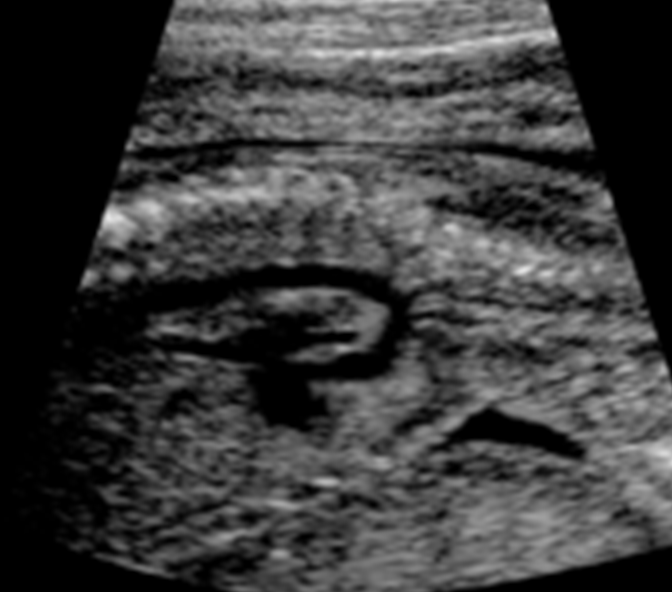

What view is this?

Crisscross view